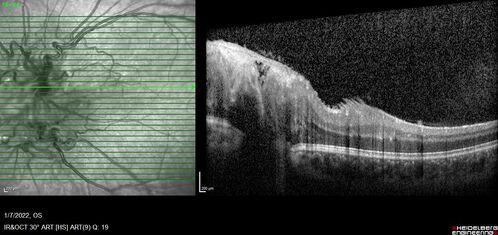

Combined hamartoma of the retina and retinal pigment epithelium

8 year old boy failed vision screening at school. VA 20/20 OD, 20/40 OS

Combined hamartoma of the retina and the retinal pigment epithelium